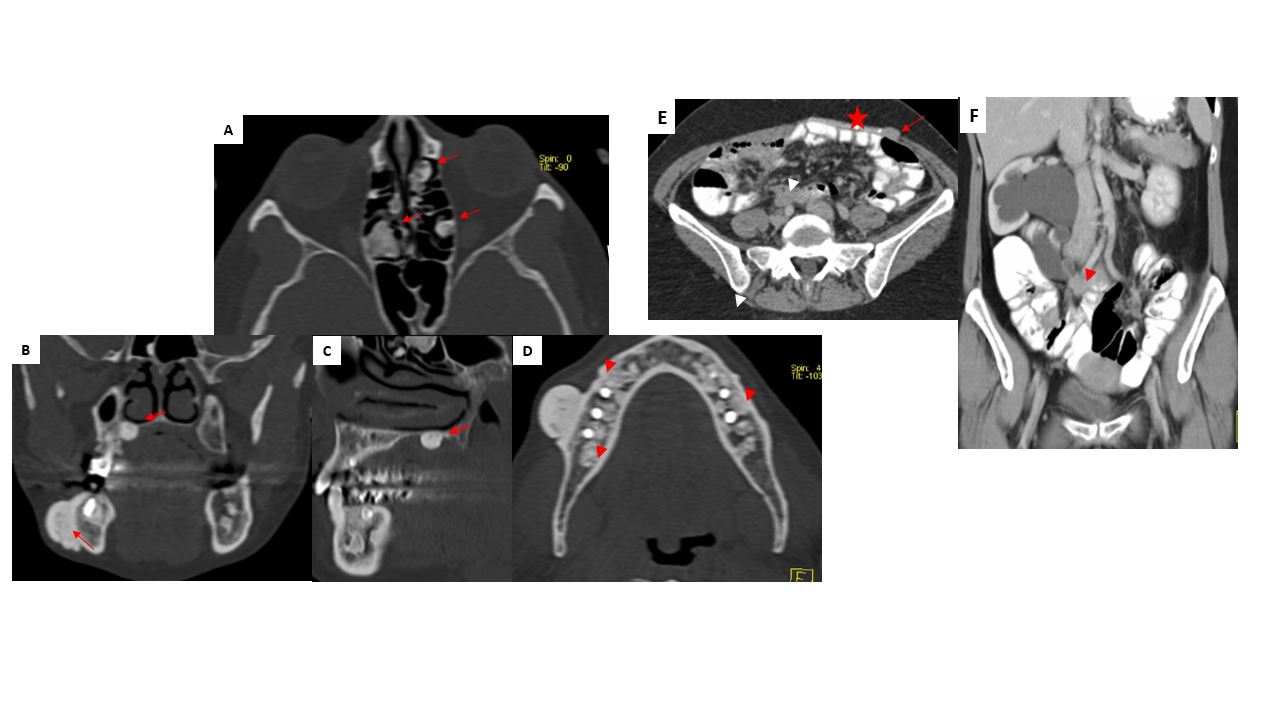

A y D: TC corte axial, ventana ósea. Múltiples lesiones radiodensas compatibles con osteomas (flechas) y odontomas (punta flecha). B: TC corte coronal, ventana ósea. C: Corte sagital, ventana ósea. Lesión radiodensa palatina (flecha doble): diente supernumerario. E: TC axial abdominal con contraste oral e intravenoso. F: TC con contraste oral e intravenoso reconstrucción coronal. Hidronefrosis derecha por atrapamiento del uréter por tumor denso e hipercaptante de morfología irregular compatible con tumor dermoide (punta flecha). Además existe tumor de similares características (flecha) adyacente a la malla metálica (*) en E.

Síndrome de Gardner

Poliposis adenomatosa familiar (PAF) asociada a otras lesiones extracolónicas en páncreas, hígado, tiroides, duodeno y estómago.

50% de pacientes con esta entidad tienen osteomas, 48% de los cuales se localizan en el cráneo y senos, y 20% en la mandíbula. Además se pueden encontrar odontomas y dientes no erupcionados y supernumerarios.

Los osteomas representan el tumor más frecuente del macizo facial. Sin embargo no es habitual la multiplicidad de lesiones. La observación de múltiples osteomas (mas de tres) asociada a anomalías dentales debe hacer incluir esta entidad en el impresión diagnóstica. Su detección precoz es importante porque existe un alto riesgo de trasformación maligna de los pólipos intestinales.